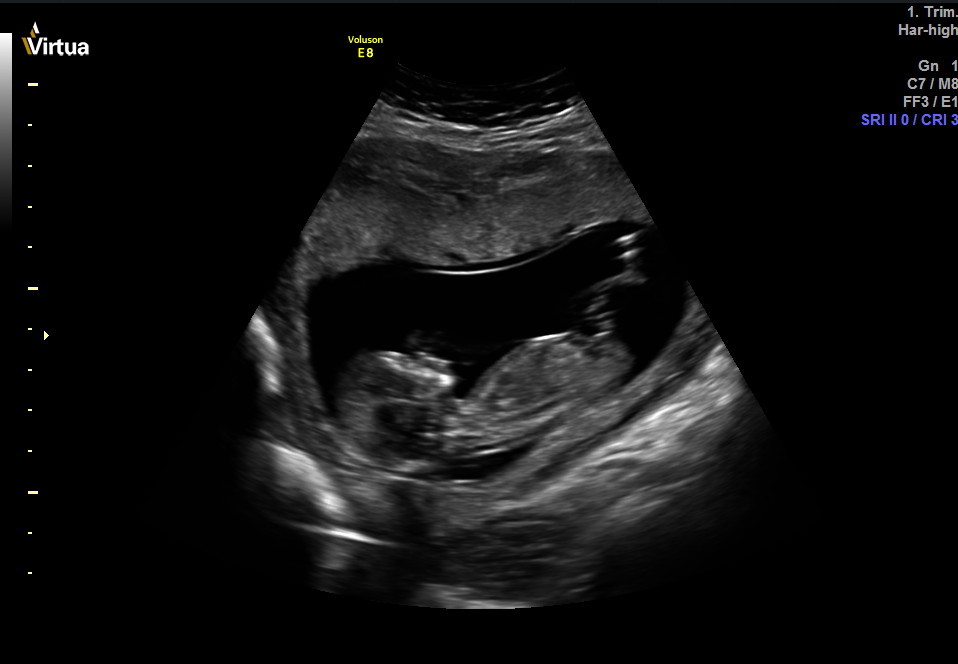

I don't see a nub, but I'm terrible at looking at these things. Can anyone guess the gender? Thank you for your help! I will come back and update on Thursday since we are going for a private scan. Hopefully baby cooperates!Attachment 34055Attachment 34056Attachment 34057Attachment 34061